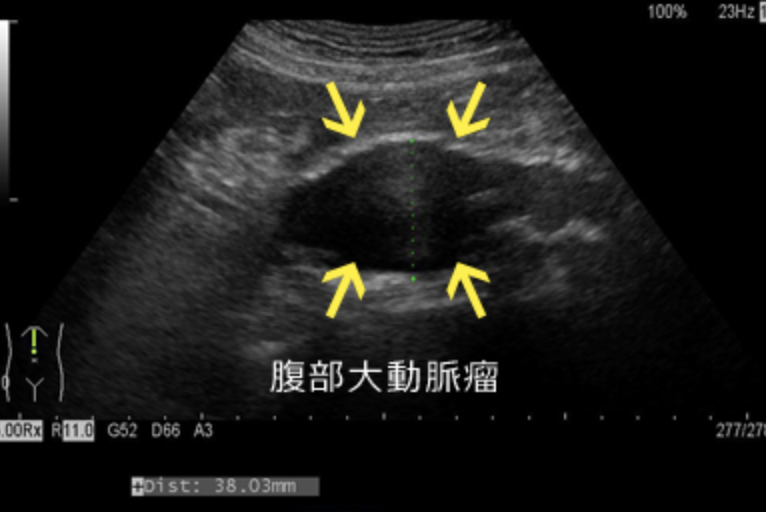

まず触診してみる。大動脈瘤径が3-4cmでは1/3で触知可能、径5cm以上でも75%程度触知可能と言われるが、体表からの触診には限界がある。高血圧の既往のある高齢患者では必ず鑑別として上げてエコーで評価する。

・超音波でみえる大動脈瘤の一例